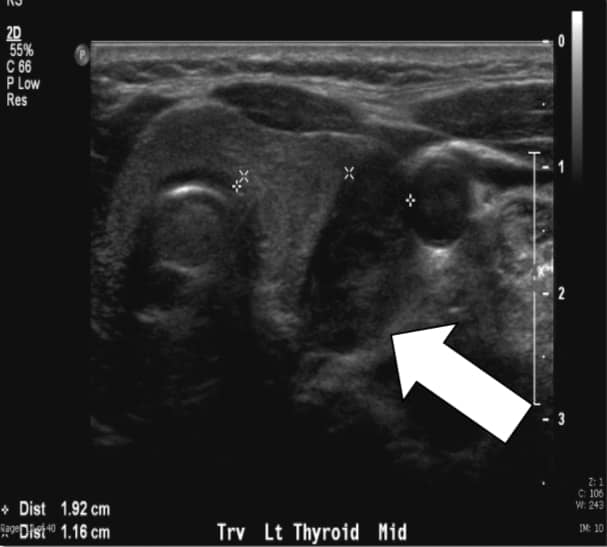

Biyokimyasal değerlendirme, toplam serum kalsiyumu 10.7 mg / dl (referans aralığı 8.8-10.2 mg / dl), yüksek PTH seviyeleri 76-81 pg / ml (referans aralığı 10-65 pg / ml) ve 24 saatlik idrar kalsiyumu 438 mg / 24 saat olan hiperkalsiüri gösterir. Preoperatif olarak hem ultrasonografi hem de tek foton emisyonlu bilgisayarlı tomografi (SPECT) ile sestamibi ile yapılan görüntülemede sol alt paratiroid lezyonu düşündürdü.

Etkili, noninvaziv ve ucuz olduğu için ultrasonu rutin olarak yapıyoruz. Kısıtlılıklar arasında hem operatör bağımlılığı hem de mediastinal adenomların boyunla sınırlı olması nedeniyle görüntülenememesi yer almaktadır. Normal paratiroid bezi genellikle sonografik olarak görüntülenemeyecek kadar küçükken, pHPT'de görülen paratiroid büyümesi genellikle homojen hipoekoik ekstratiroidal oval kitle olarak tanımlanır. Paratiroid adenomları tipik olarak vaskülerdir ve sıklıkla lezyonun üst veya alt kutbuna kadar bir arteriyel dal takip edilebilir. Kendi başına, ultrason yaklaşık% 50-75'lik bir gerçek-pozitif orana sahiptir ve daha büyük bezler için genellikle daha iyi oranlara sahiptir. 2